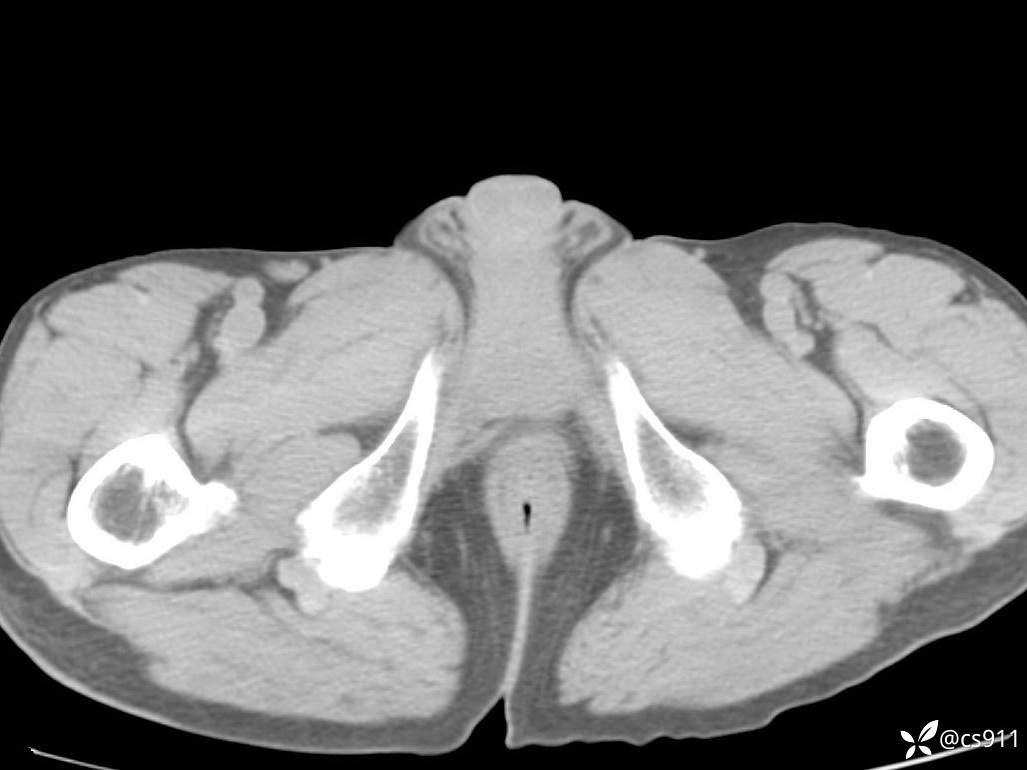

男,77岁,腹痛、腹胀伴恶心呕吐1天。呕吐胃内容物,非喷射性呕吐,有咖啡色样胃内容物,诉有胃穿孔病史。查体:全腹平,下腹部压痛,全腹无反跳痛,叩诊呈浊音,移动性浊音阴性,肠鸣音减弱,1-2次/分。肛检:直肠未扪及明显肿物,可触及大量粪块。